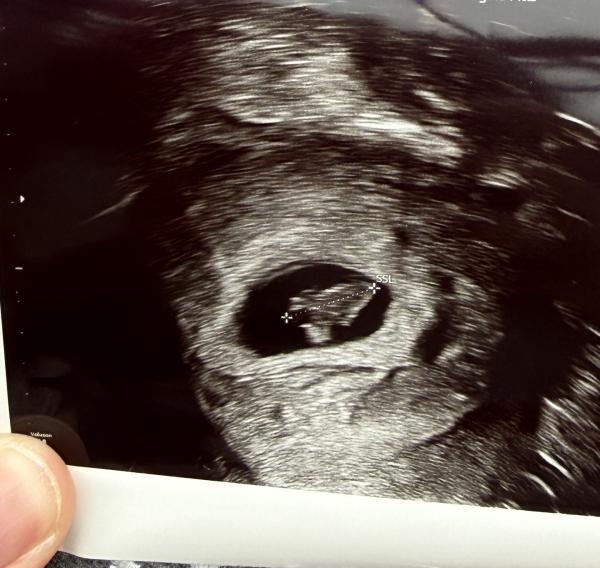

Hallo  ich bin jetzt bei 13+2 Habe hier ein Bild von 7+4 mich interessiert was die ramzi Methode sagt. Mein bauchgefühl ist Mädchen. Wenn wer es erkennt gerne schreiben ☺️ Ist aktuell die 3 Schwangerschaft  Bild 1 ist aktuelle (7+4) Bild 2 ist 2 Schwangerschaft ist ein Mädchen (6+1) Bild 3 ist 3 Schwangerschaft ist ein Junge (6+4)